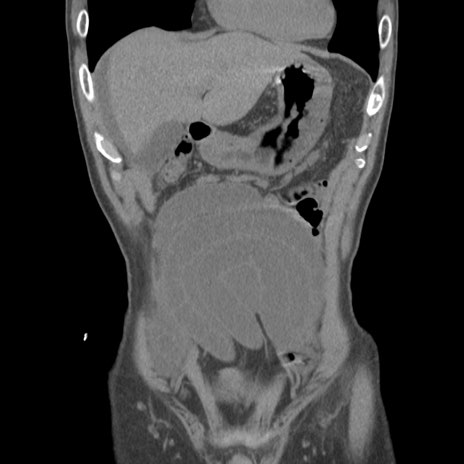

症例56 CT(冠状断像)

横断像